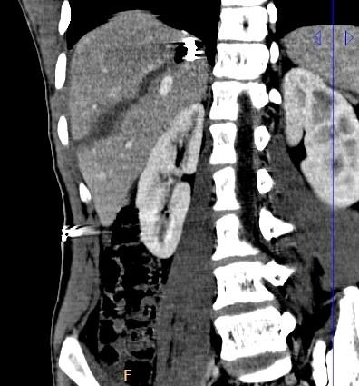

CT决定手术或介入或保守治疗,没有CT就没有介入治疗 并没有出血,保守治疗是个选择 Increasing use of endovascular therapy in acute arterial injuries analysis of the National Trauma Data Bank J Vasc Surg.

CT决定手术或介入或保守治疗,没有CT就没有介入治疗

并没有出血,保守治疗是个选择